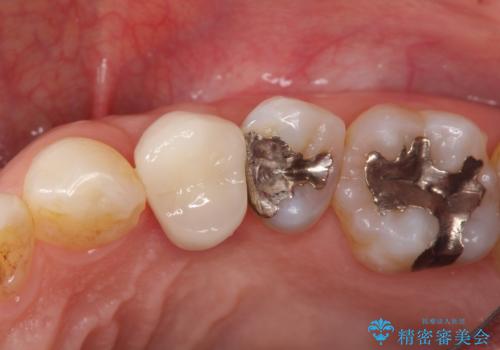

- 歯肉の下まで深く歯が折れたことを主訴に来院された患者様です。

かかりつけ医にて応急的に修復してますが根本的な治療を希望され、矯正的挺出を行ったのち、歯周外科を行い、歯冠修復をしております。

歯肉縁下の水平破折をきちんと治療するためには時間も費用もかかります。